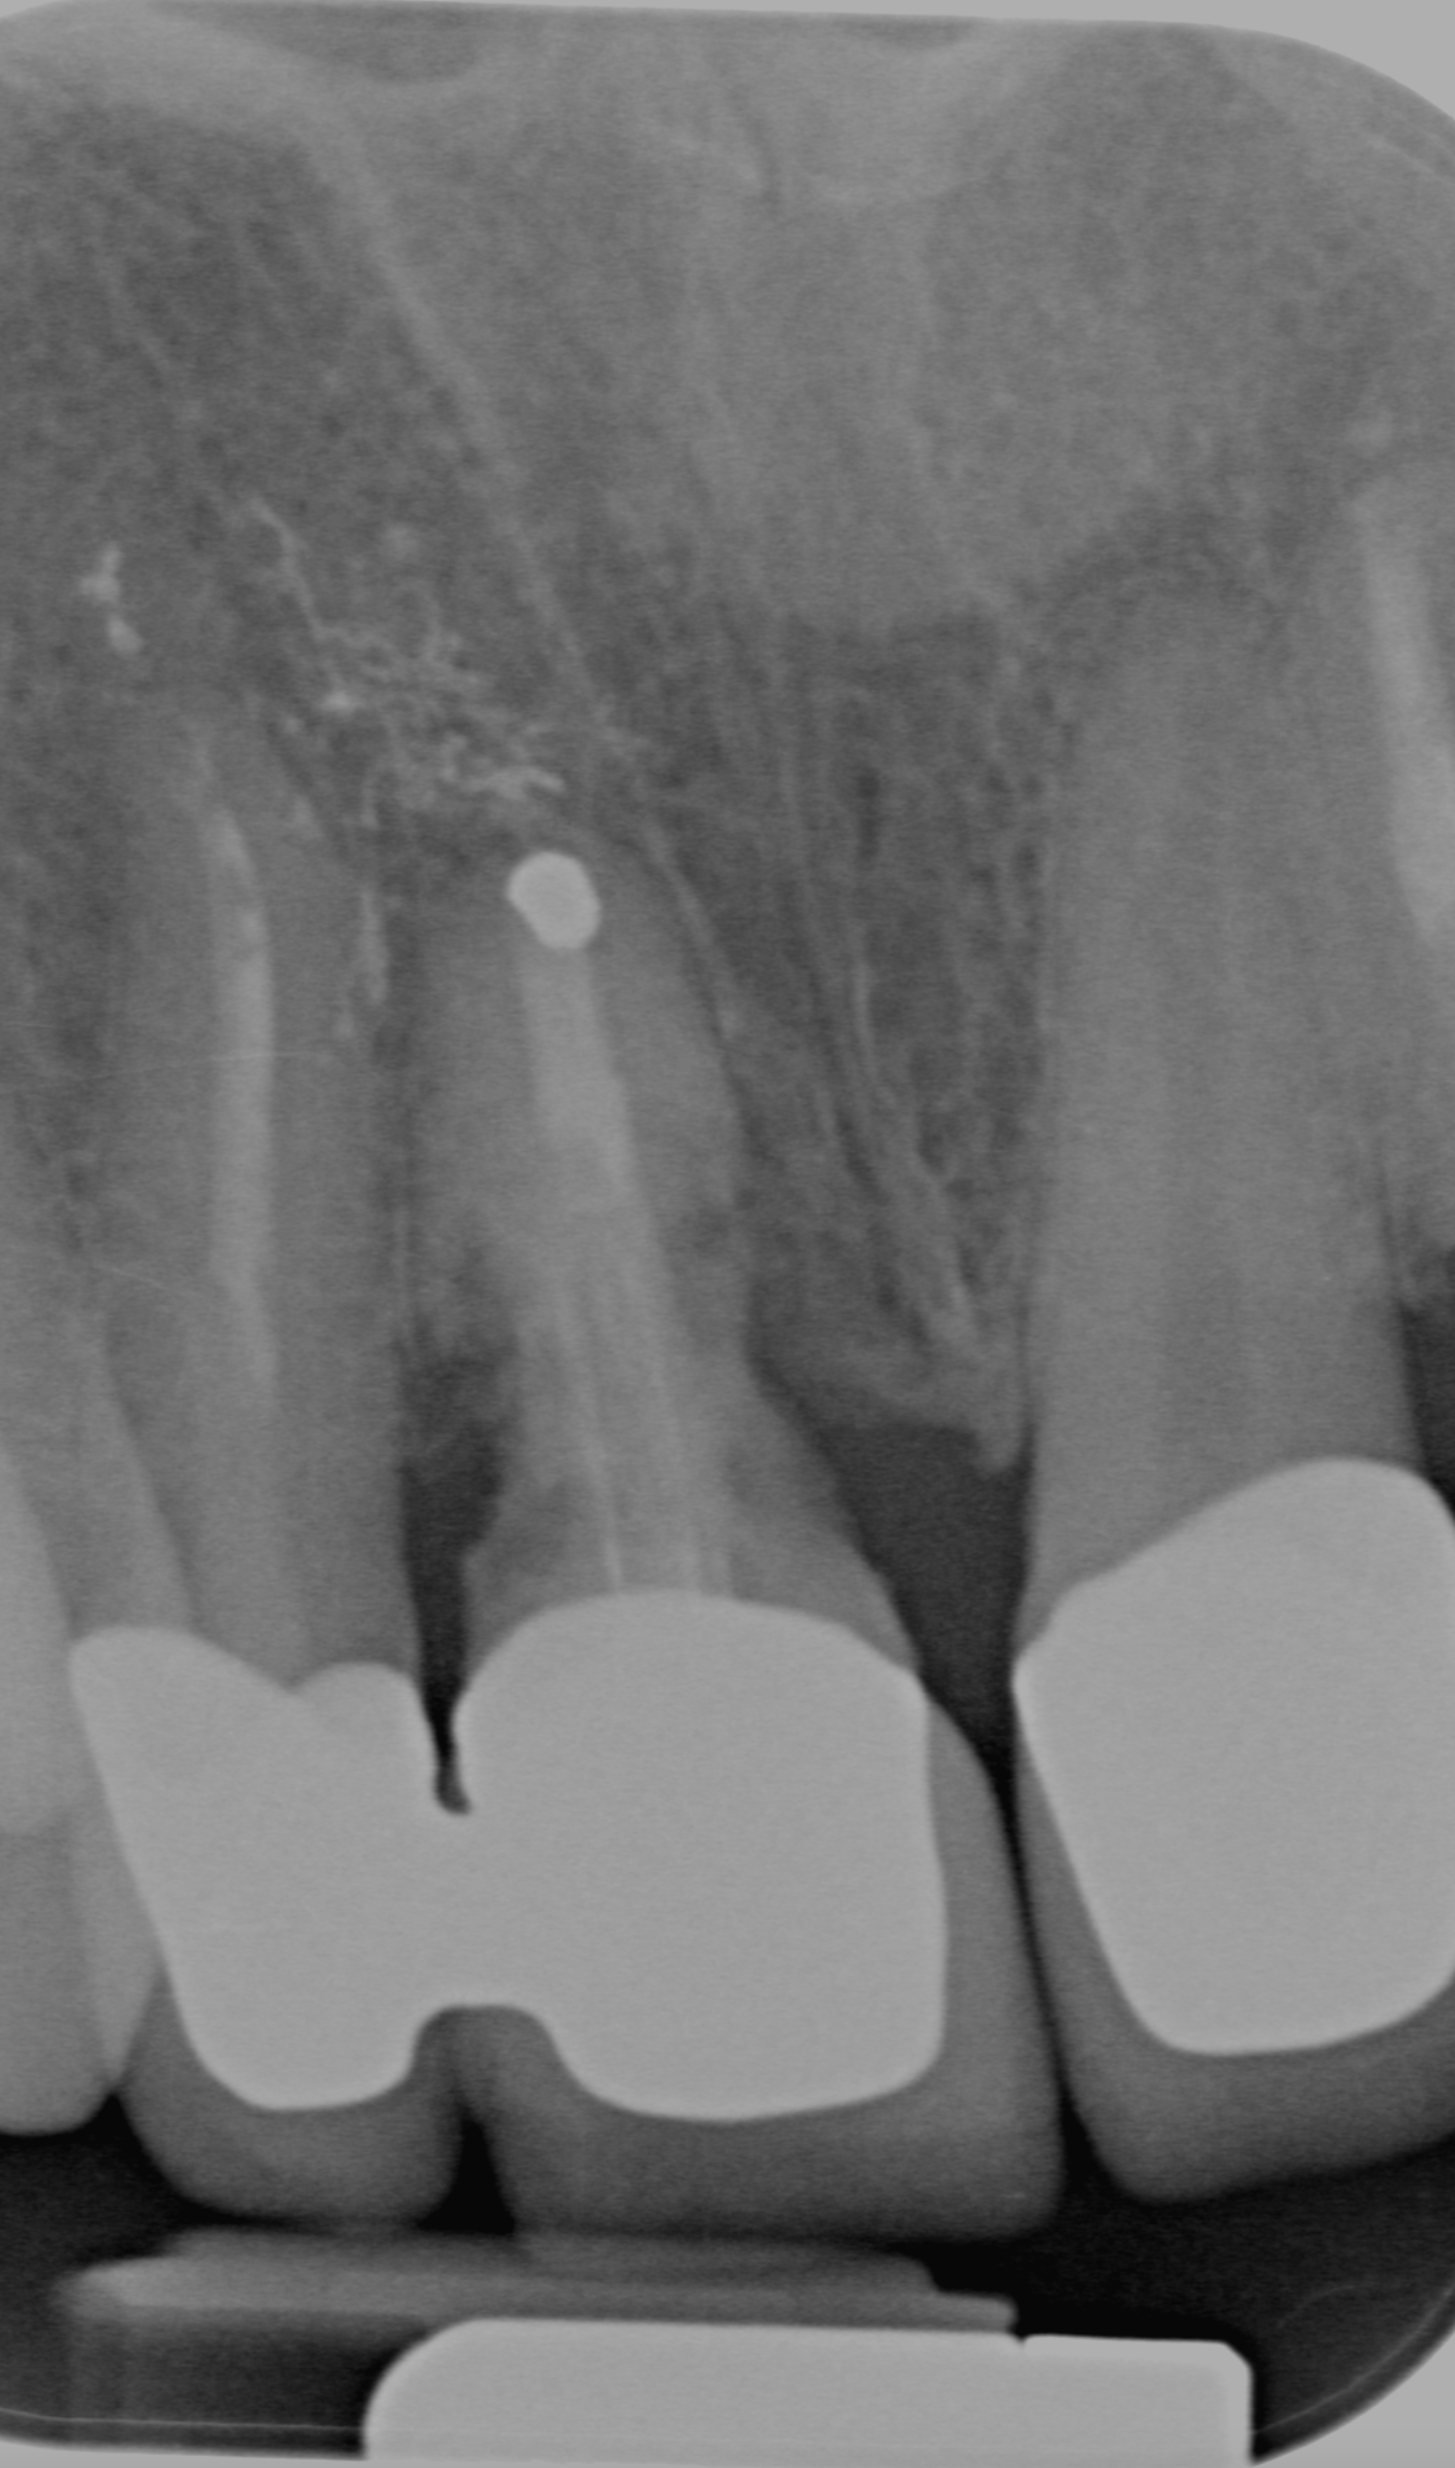

La paziente ha subito un trauma sugli elementi frontali nel 2000. I denti sono stati recuperati e riabilitati protesicamente con corone fisse sulle radici naturali. Dopo più di 20 anni, l’elemento 11 mostra segni di riassorbimento radicolare (tipico dei denti traumatizzati). Si procede con la sostituzione dell’elemento con un impianto singolo.

PRIMA